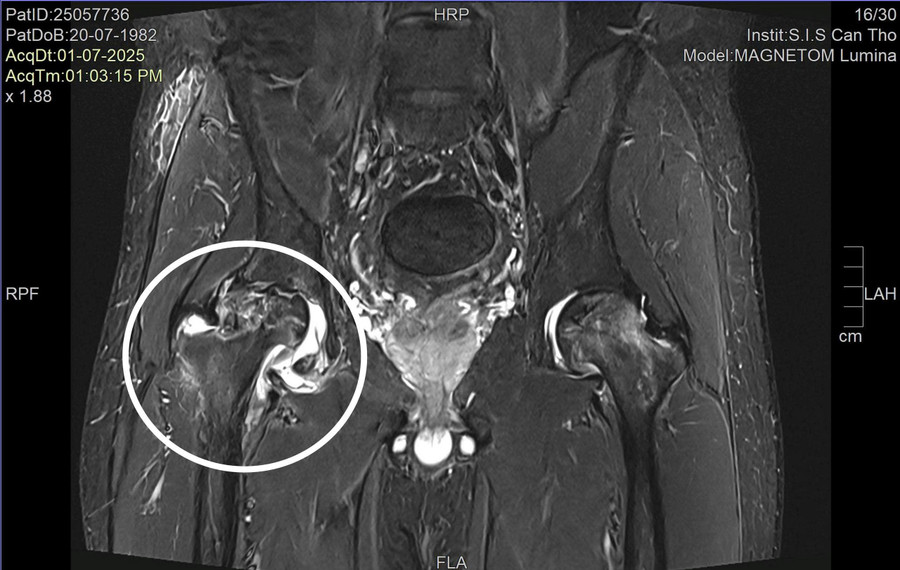

Theo ThS.BSNT.CKI Nguyễn Trần Duy, Khoa ngoại tổng hợp, kết quả thăm khám và chụp chiếu tại bệnh viện cho thấy bệnh nhân bị hoại tử chỏm xương đùi cả hai bên, với mức độ hoại tử bên phải là độ 3 và bên trái độ 2.

Đây mới là nguyên nhân thực sự gây đau nhức vùng hông và hạn chế vận động của bệnh nhân.

Hình ảnh MRI ghi nhận hoại tử chỏm xương đùi. Ảnh: BVCC.